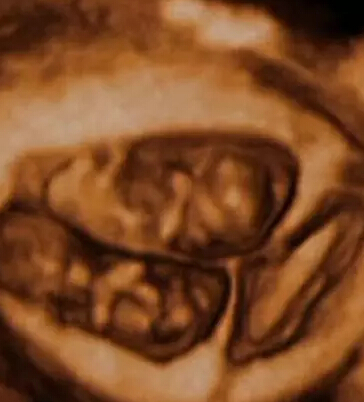

双胞胎在上演“子宫中接吻”。多胞胎被认为因子宫中的互动而受益,这些互动有助于他们更快地发育。

这部名为《子宫里:双胞胎、三胞胎和四胞胎》的纪录片,通过计算机生成图像,将真实扫描数据制作成令人叹为观止的画面。

看到他们脸部表情的细节,比如微笑和眨眼,还有多胞胎之间的互动,都让我感到非常震惊。“